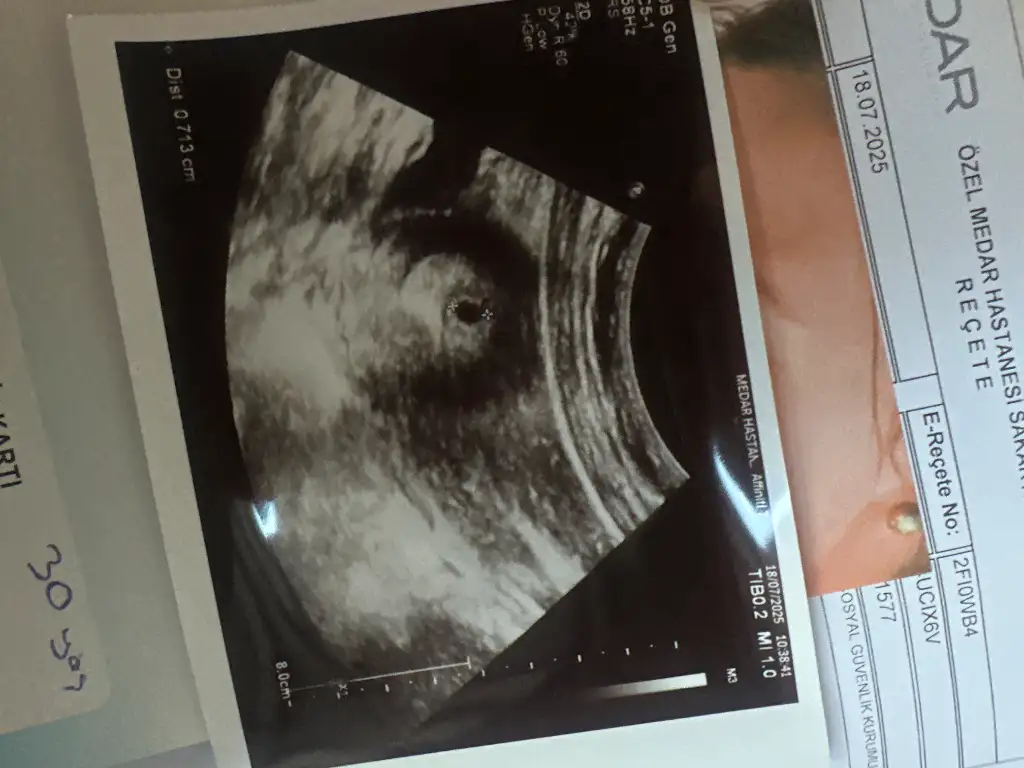

Kızlar bende 6 haftalık hamileyim. Keseyi gördük kalp atışı 10 gün sonra inşllah . Yalnız vajinamda baskı hissi var sanki doğum yapacak mışım gibi. Erken gebelikte normal mi bu

Merhaba, doktordan çıktım şimdi. 5+6'yım. Kalp atışını duyamadık ama kalbinin yanıp sönmesini gördüm, ışık gibi daha çok küçük haftaya duyabiliriz dedi doktorum. Bebeğimin boyu 2 milimmiş. Her şey yolunda görünüyor, ama sesini duymamak tabi endişe veriyor

bende 5+2 de keseyi gördüm, pazartesi 6+4 de kalp atışı için çağırdı bakalım duyabilecek miyiz